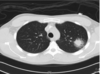

48

מהו הממצא

בקטריות לא טיפוסיות , קורונה דלקת ריאות שהיא patchy A-typical pneumonia